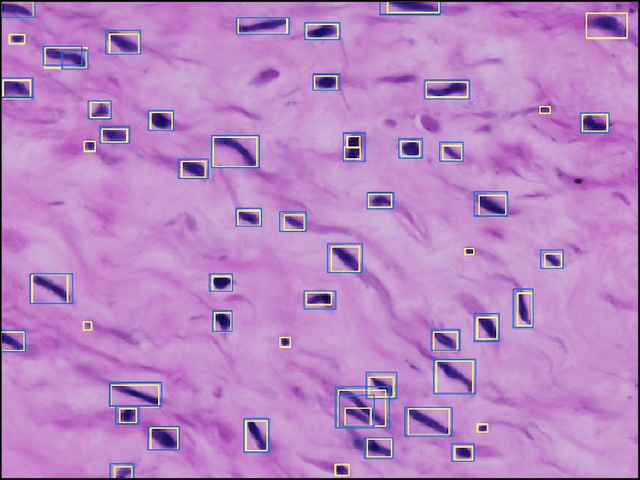

Abstract:The placenta is a complex organ, playing multiple roles during fetal development. Very little is known about the association between placental morphological abnormalities and fetal physiology. In this work, we present an open sourced, computationally tractable deep learning pipeline to analyse placenta histology at the level of the cell. By utilising two deep Convolutional Neural Network architectures and transfer learning, we can robustly localise and classify placental cells within five classes with an accuracy of 89%. Furthermore, we learn deep embeddings encoding phenotypic knowledge that is capable of both stratifying five distinct cell populations and learn intraclass phenotypic variance. We envisage that the automation of this pipeline to population scale studies of placenta histology has the potential to improve our understanding of basic cellular placental biology and its variations, particularly its role in predicting adverse birth outcomes.